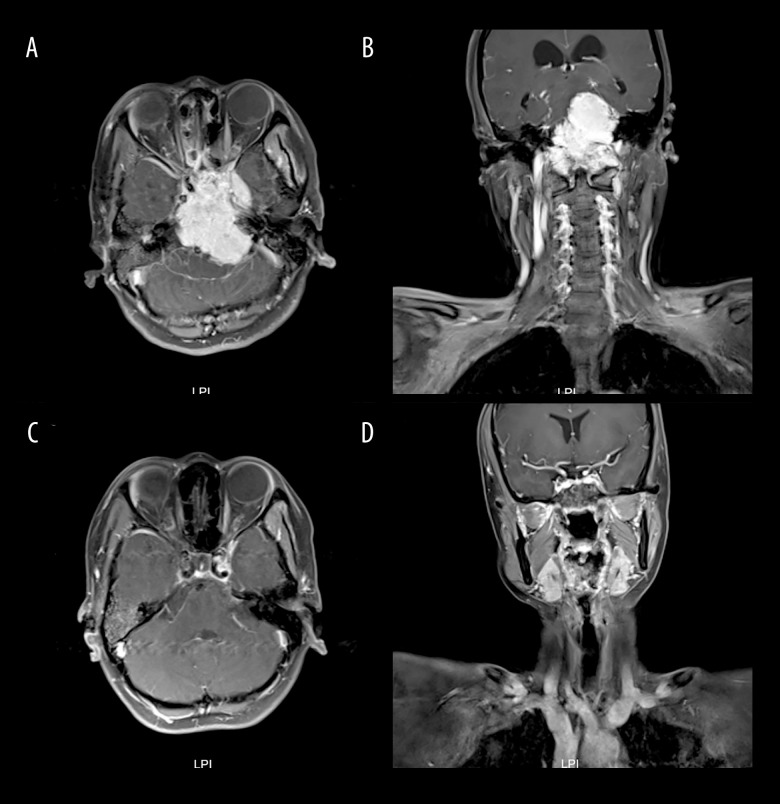

BACKGROUND Nasopharyngeal carcinoma can directly invade the intracranial cavity through skull base foramina in advanced-stage patients. Due to both the multiple cranial nerve injuries associated with nasopharyngeal base invasion and the proximity of the pituitary gland, it is challenging to differentiate this condition from intracranial space-occupying lesions, such as meningiomas and pituitary adenomas, in the early stages. This report describes a 37-year-old woman with bilateral nasal congestion, diplopia, hearing loss, and headache diagnosed with a large nasopharyngeal carcinoma invading the cerebellum, pons, medulla oblongata, and cervical spinal cord. CASE REPORT A 37-year-old woman with nasopharyngeal carcinoma (NPC) exhibiting extensive intracranial invasion - involving the mesencephalon, cerebellum, pons, medulla oblongata, and cervical spinal cord - was, with difficulty, diagnosed as having intracranial space-occupying lesions (meningiomas/pituitary tumors) by some renowned neurosurgical centers. She came to our hospital using a wheelchair, exhibiting vague pronunciation, decreased bilateral hearing, headache, facial numbness, diplopia, and coughing when drinking water. Following definitive diagnosis through nasopharyngeal biopsy confirming non-keratinizing carcinoma, we quickly proceeded with treatment. After receiving 6 cycles of chemotherapy with anti-PD-1 immunotherapy, followed by tomotherapy with concurrent nivolumab, the lesion was dynamically reduced, and efficacy was assessed as a complete response (CR). Therapy significantly improved her symptoms, with the holocranial headache resolving, intelligible speech restored, and facial sensation recovered. CONCLUSIONS This case highlights the importance of routinely integrating nasopharyngeal MRI and biopsy when evaluating patients with atypical cranial neuropathies. Furthermore, multidisciplinary team (MDT) collaboration is essential to avoid delayed diagnosis in NPC cases with extensive skull base invasion.